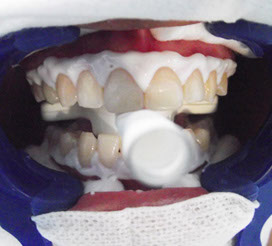

El blanqueamiento láser consiste en aplicar sobre los dientes un gel a base de peróxido de hidrógeno al 25% cuyo efecto se activara al momento de aplicar la luz foto láser emitida que es inferior a los 400 nm, el resultado: dientes libres de manchas, blancos y brillantes.

Esta técnica se realiza en consultorios de dentistas o en clínicas dentales, en Dental Evolution en Cancún poseemos la tecnología, que nos permite realizar con maravillosos resultados este procedimiento.

¿Cuántas veces tengo que acudir con el dentista para que mi tratamiento esté terminado?Es posible que usted tenga que recibir primero una limpieza en la que se elimine la placa bacteriana y de esta forma dejar preparados sus dientes para una segunda consulta en la que se aplicara el procedimiento, el blanqueamiento láser por si solo, se lleva a cabo en una sola consulta, todo depende de cada caso en particular.

El blanqueamiento láser arroja resultados inmediatos usted se ira a su casa con los dientes limpio, blancos y brillantes.